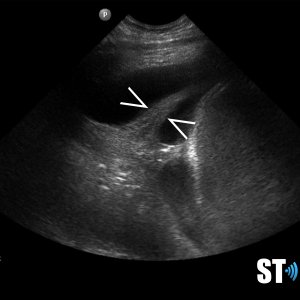

Pleural Effusion

Pleural effusion is a build up of fluid between the layers of the pleura. Scanning subcostally will show fluid above the diaphragm. Scanning intercostally will show fluid anterior the lung. Common causes for pleural effusion is infection, inflammation and malignancy.

The fluid can be anechoic or echogenic in cases of increased exudates, empyema, hemothorax and chylothorax (lymph collection). There may also be septations.

Pleural effusion can have transudative and exudative causes. Transudate is fluid pushed through the capillary due to high pressure within the capillary. Exudate is fluid that leaks around the cells of the capillaries caused by inflammation.